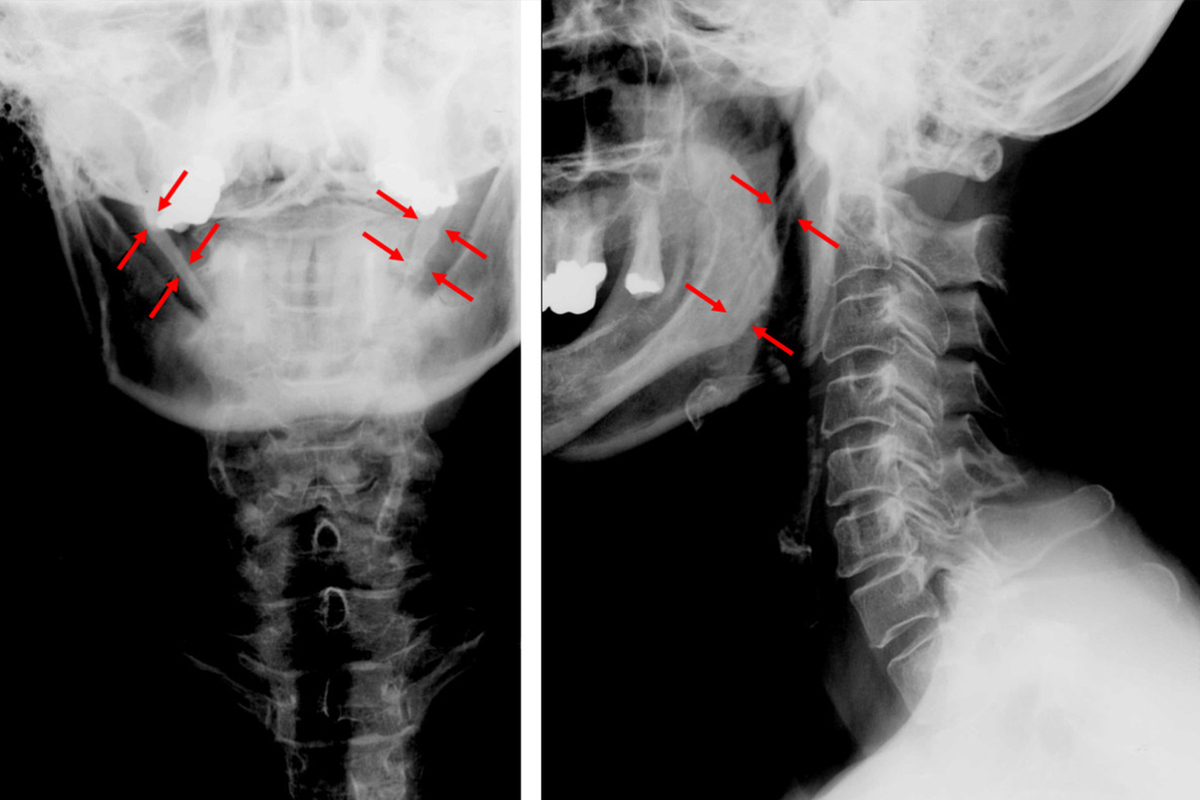

Мальчика с редчайшей генетической патологией - синдромом Игла - прооперировали в Москве. Чрезмерно удлиненные отростки черепа сдавливали сосуды и нервы шеи, вызывая нестерпимую боль при каждом движении ребенка головой.

На КТ было обнаружено аномальное удлинение шиловидных отростков — костных выступов у основания черепа. В норме их длина не превышает 3 сантиметров. А у ребенка они выросли до 6 сантиметров с каждой стороны.  Это заболевание обычно встречается только у взрослых пациентов в возрасте 30–50 лет. Отростки удлиняются за счет окостенения шилоподъязычной связки. Точные причины этого процесса неизвестны. Но иногда эта связка может начать накапливать кальций на фоне множественных инфекционных заболеваний ротоглотки.

Безопасно удалить эти длинные части, не повредив саму шею, было крайне сложно. Врачи использовали доступ через естественную складку на шее. Во время операции им удалось отделить отростки от сосудисто-нервных пучков и удалить их практически без кровопотери. Боль при поворотах головы перестала беспокоить мальчика сразу же после операции.